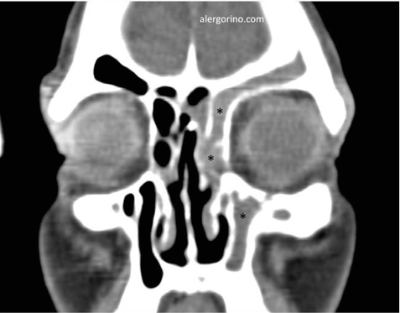

El diagnóstico se realiza mediante la historia clínica y una endoscopia nasal que proporcionan datos como la presencia de pólipos, la descarga mucopurulenta y el edema o la obstrucción de las áreas de drenaje de los senos paranasales. Si no se produjera una respuesta al tratamiento médico se evalua la situación de los senos paranasales mediante una tomografía computarizada (TC).

tomografía computarizada sinusitistomografía computarizada sinusitis tomografía computarizada sinusitis crónicatomografía computarizada sinusitis crónica